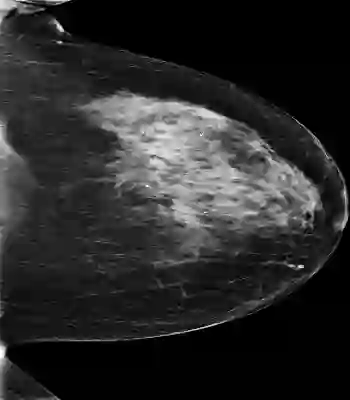

Mammography is used as a standard screening procedure for the potential patients of breast cancer. Over the past decade, it has been shown that deep learning techniques have succeeded in reaching near-human performance in a number of tasks, and its application in mammography is one of the topics that medical researchers most concentrate on. In this work, we propose an end-to-end Curriculum Learning (CL) strategy in task space for classifying the three categories of Full-Field Digital Mammography (FFDM), namely Malignant, Negative, and False recall. Specifically, our method treats this three-class classification as a "harder" task in terms of CL, and create an "easier" sub-task of classifying False recall against the combined group of Negative and Malignant. We introduce a loss scheduler to dynamically weight the contribution of the losses from the two tasks throughout the entire training process. We conduct experiments on an FFDM datasets of 1,709 images using 5-fold cross validation. The results show that our curriculum learning strategy can boost the performance for classifying the three categories of FFDM compared to the baseline strategies for model training.